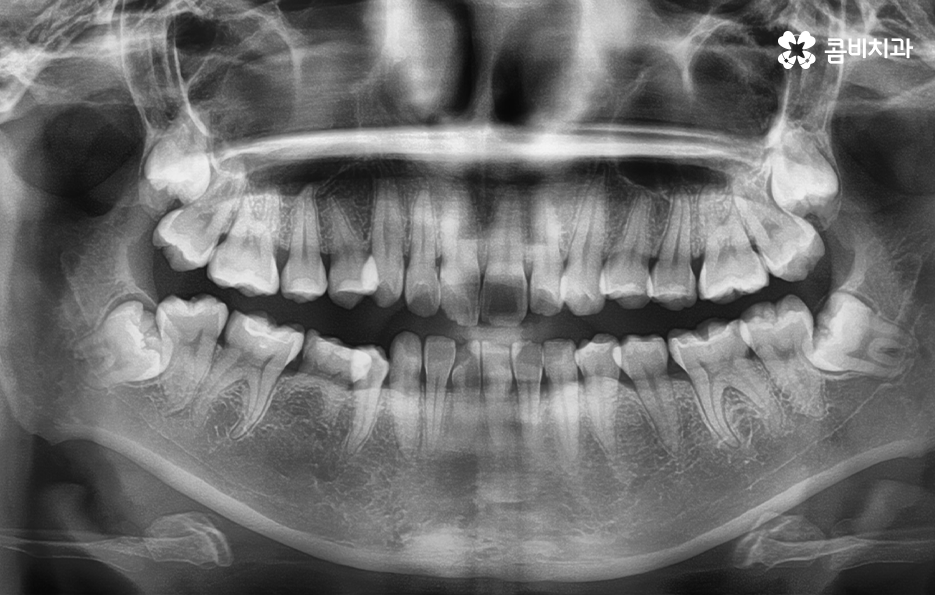

덧니라고 함은 치아의 정상적인 배열에서 많이 벗어난 치아를 의미하고 있는데요. 덧니가 발생하는 원인은 유전적인 원인부터 안좋은 습관 등 다양하겠지만 일반적으로 영구치가 나올 무렵에 치아가 정상적으로 나올 공간이 부족한 상태에서 치아가 맹출되다 보니 덧니가 발생하는 경우가 대표적이라 할 수 있어요

덧니는 윗니와 아랫니에 모두 있거나 앞니에 살짝 있는 수준의 덧니도 있으며 덧니가 심한 경우에는 개방교합으로 인해 입이 잘 다물어지지 않는 경우도 있기 때문에 덧니가 심한 정도에 따라서 치아교정의 계획은 세부적으로 달라질 수 있어요

덧니가 심하지 않은 경우에는 비발치로도 충분히 교정을 하는 경우도 있겠지만 덧니가 심한 경우에는 덧니 발치 교정을 통해서 치료가 진행되는 경우가 많이 있는데요. 그 이유는 치아교정의 원리를 생각하더라도 치아를 재배치하기 위해서는 기존의 치아가 움직일 공간이 필요한데 덧니는 치열이 이미 완성되고 있는 상태에서 치아가 나올 공간이 부족하여 덧니가 되는 경우가 많다는 점에서도 치아의 이동 공간을 확보하기 위한 발치가 필요할 수 있는 거예요